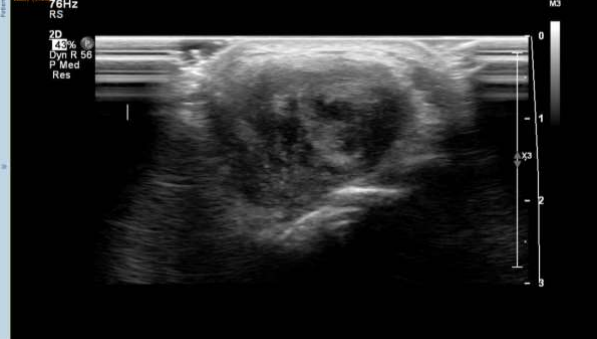

The patient had a solid hypoechoic lobulated mass lesion measuring 27x16mm on the dorsal aspect of his left wrist. The diagnosis was a giant cell tumor and soft tissue sarcoma, and fur-ther investigations were advised. X-rays showed a soft tissue shadow in the lateral view, but no bony abnormalities were noted. MRI scans revealed an irregular, intensely enhancing soft tissue mass at the wrist's dorsal aspect, interposed between the 4th and 5th extensor tendon compartments. The MRI findings were consistent with a benign soft tissue neoplasm.

The features of nodular fasciitis on ultrasound and magnetic resonance imaging (MRI) are non-specific, with the lesions appearing as well-circscribed, round to oval masses. Signal intensity of the condition is variable, with intramuscular lesions appearing mildly inhomo-geneous and hyper intense to skeletal muscle on T1-weighted spin-echo images, and subcu-taneous lesions being markedly hypo intense to skeletal muscle on all spin-echo sequences and appearing homogeneous in texture. High cellularity and micro-vessel density may di-rectly influence the early enhancement after intravenous gadolinium injection and compact cellularity with a prominent capillary network. A myxoid pattern may be responsible for the enhancement on MRI (7,8).

Figures 1,2,3,4,5,6

Figure 2